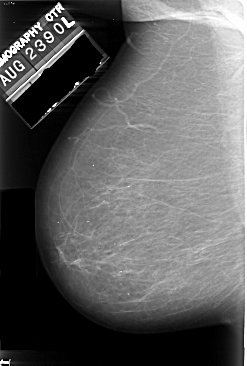

A_1005_1.LEFT_MLO

ics_version 1.0

filename A-1005-1

DATE_OF_STUDY 23 8 1990

PATIENT_AGE 78

FILM_TYPE REGULAR

DENSITY 2

DATE_DIGITIZED 16 12 1997

DIGITIZER DBA 21

LEFT_MLO LINES 5476 PIXELS_PER_LINE 3691 BITS_PER_PIXEL 16 RESOLUTION 42 NON_OVERLAY